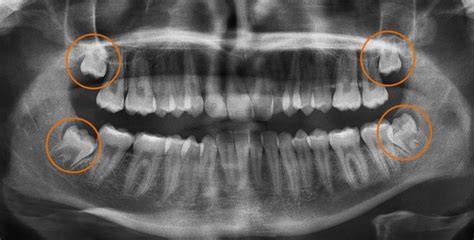

Los problemas provocados por las muelas del juicio se diagnostican con una simple radiografía. En general, estos problemas se detectan en la adolescencia o juventud. Las personas mayores de 30 años no suelen tener problemas que requieren la extracción de las muelas del juicio.

La formación de estos dientes se inicia a partir de los 12 años y el dentista puede ver, por medio de una radiografía panorámica (ortopantomografía) si aquella persona tiene o no muelas del juicio. Esta exploración por imagen también permite saber si las piezas están creciendo bien o no, si se han quedado dentro del hueso y, por tanto, no aparecen en la encía.